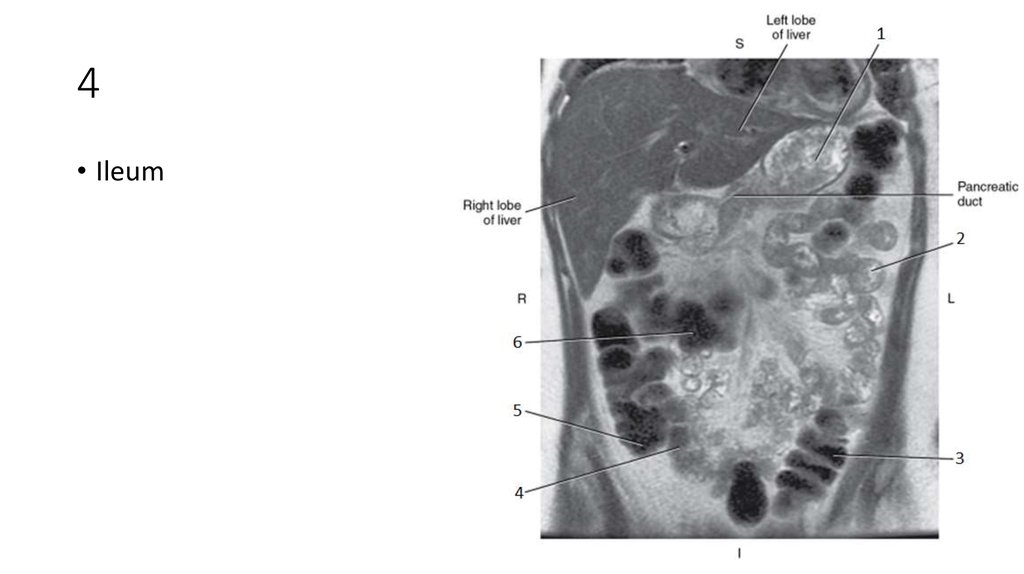

56. 4

57. 4

• Ileum